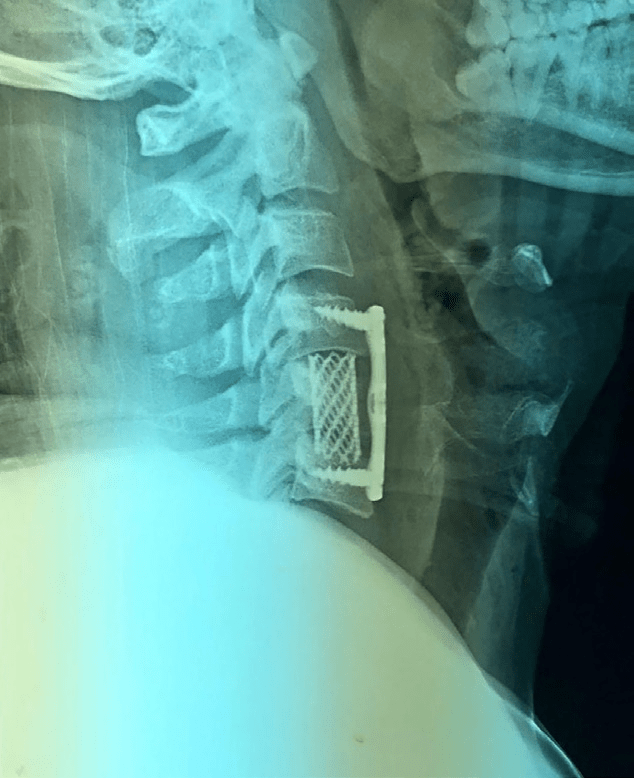

Se inicia manejo analgésico e inmovilización con collarín rígido tipo Philadelphia, se programa para manejo quirúrgico a base de “Artrodesis anterior C4-C6 con placa cervical con matriz ósea+malla de titanio” (Figs. 3 y 4)